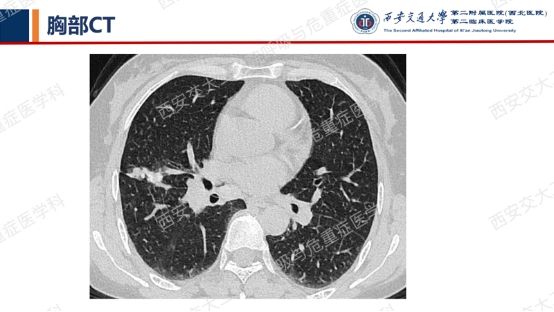

第一期埋下的伏笔,以下2例不同患者的胸部影像改变,又分别考虑什么疾病呢?答案呼之欲出,相信大家也越来越清晰了!